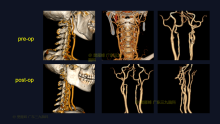

除了PEEK 钛网 本次用了超高分子量聚乙烯 颅骨修补

脑血管-烟雾病